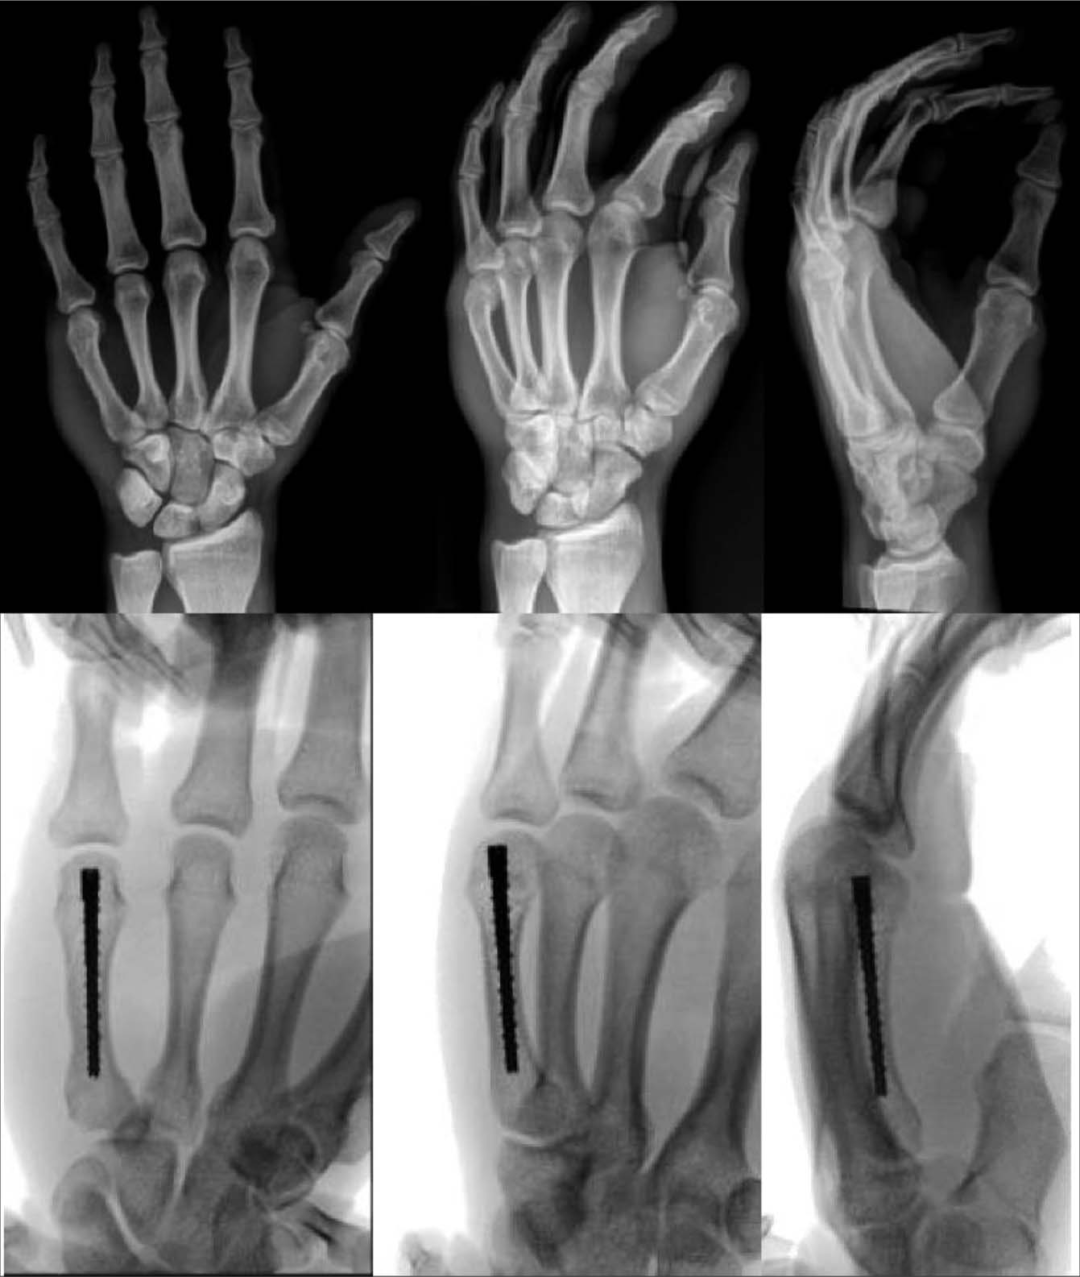

对于远端骨量充足的骨折,髓内固定的应用可能是可行的(图2)

髓内治疗可用于固定的骨量充足的骨折。

髓内螺钉可以是一种安全的技术,即使对于粉碎性或螺旋型骨折,也可以最大限度地减少手术时间。